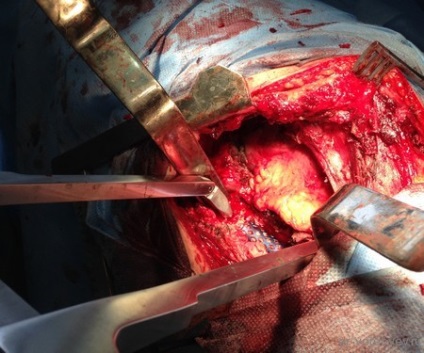

După un curs de detoxifiere și terapia masivă cu antibiotice pacientul a fost pregătit pentru o intervenție chirurgicală. Sa decis să efectueze îndepărtarea corpurilor vertebrale L1 L2 și discul între ele, iar placa corporodesis Masham umplut de os proprii (în acest caz, o margine) în China. Cel mai adesea, atunci când aveți nevoie pentru a manipula 1 vertebre vom trata accesul antero lateral deasupra sau dedesubtul diafragmei. În această situație, operarea cu cotorul de tranziție care implica doua fuziune vertebre apare între TN12 și L3, în total 4 trebuie să expună o vertebră și, prin urmare, a trebuit să folosească TORAKOFRENOLYUMBOTOMIYU. Accesul de-a lungul marginii cu deschiderea cavității pleurale și disectia retroperitoneale și diafragmei pe dreptul său semiperimetrul.

stadiu vizibil de funcționare după instalarea plasei între corpurile vertebrale. Operarea peste toracostomie placa spondylosyndesis (care a fost distrusă după ce a suferit purulent pleurita).